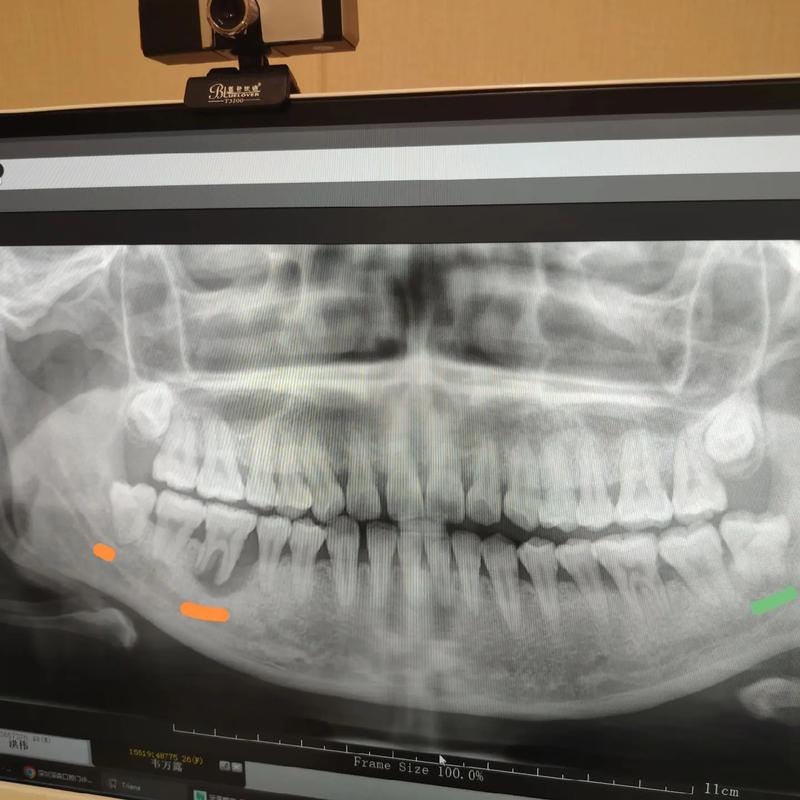

正畸前的风险评估与预防是关键环节,在正畸设计初期,应通过全口曲面断层片、CBCT等影像学检查评估智齿位置、萌出方向及与邻牙关系,对于存在高危因素的患者(如智牙胚近中角度>30°、与第二磨牙间距<5mm、牙弓后段拥挤),可考虑在正畸治疗前预防性拔除智齿,尤其当正畸方案需拔除前磨牙时,提前拔除智齿可避免其与后牙段移动的相互干扰。